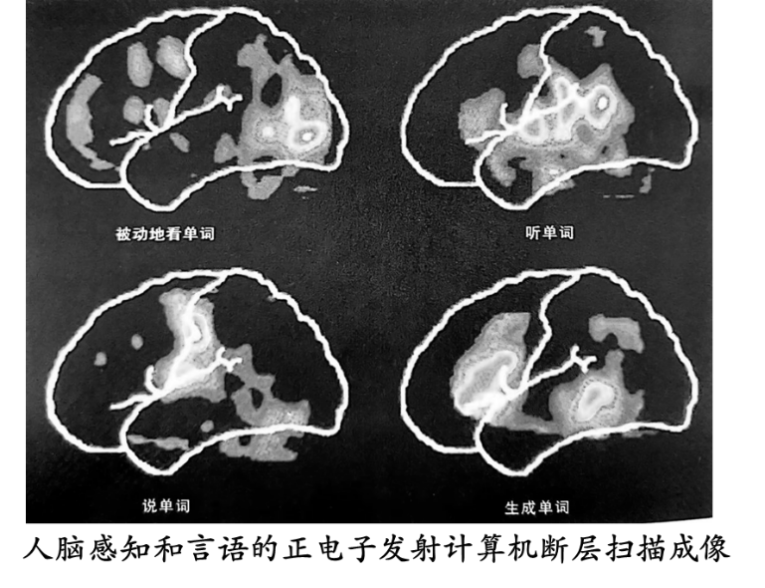

分析资料2人脑感知和言语的正电子发射计算机断层扫描成像

1脑部血流量的变化有什么检测意义?

2请你在同一张大脑图像中标注看、听、说、联想生成单词时血流量较多的位置。(思考,解读图像,标注图像)